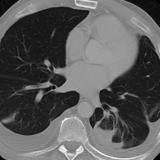

Rounded atelectasis case 1 CT